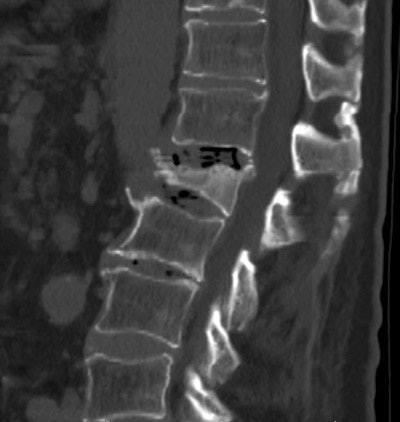

The study evaluated bone mineral density from existing CT scans compared with existing DEXA data in a smaller patient population. The study focused on the L1 vertebrae because it is easily identifiable as the first nonrib-bearing vertebra on thoracic and abdominal scans, Pickhardt said, adding that levels L1 through L5 all were evaluated and showed little variation.

Along with the conventional DEXA exams, CT bone mineral density was measured by choosing a region of interest over vertebral trabecular bone, and measuring Hounsfield units, being careful not to exclude areas that might distort the reading.

"You can't really talk in terms of accuracy, because it's very hard to compare the DEXA [to CT], but it's pretty clear that when somebody has a 100 HU or lower in the spine, [the patient] is very likely to have osteoporosis, and they might even have a fracture that we can directly see," Pickhardt said. "A lot of these people have been unscreened, or even missed at DEXA, so it's something that radiologists and others need to be aware of."